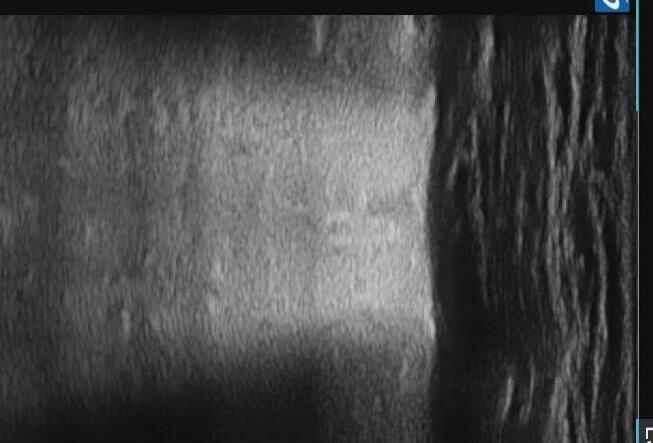

Pediatric COVID-19: MIS-C

Thoracic abnormalities

Cardiovascular abnormalities

Cardiomegaly

CHF or cardiogenic edema

Pulmonary parenchymal abnormalities

Lower lobe atelectasis

Bilateral opacities( ARDS)

Consolidation

Pleural abnormalities

Small pleural effusion

Mediastinal and hilar lymphadenopathy